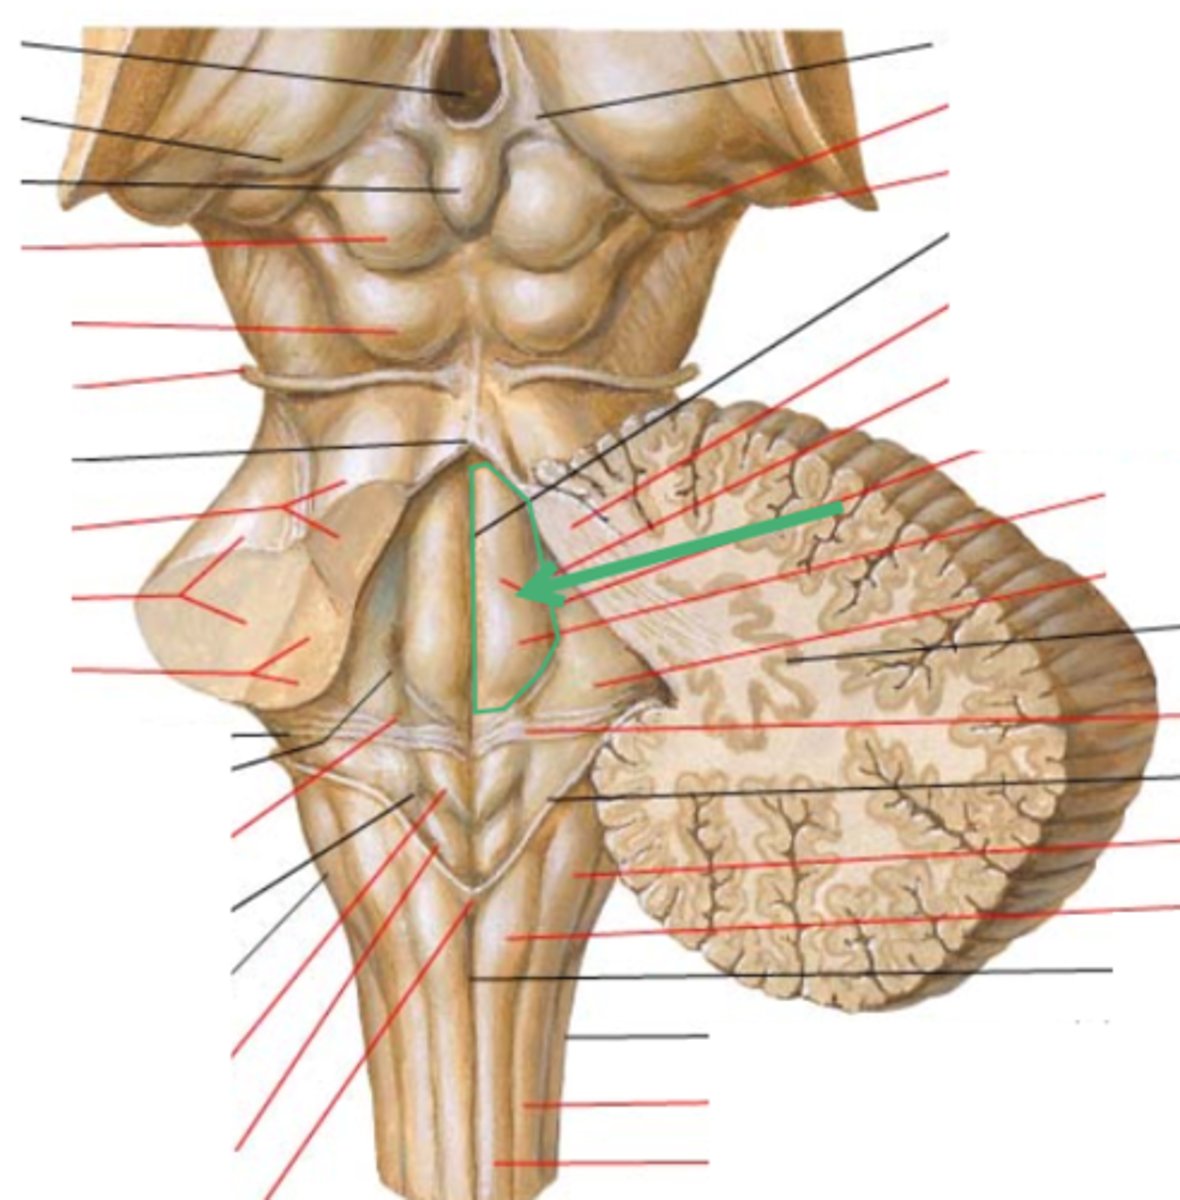

What is the superior boundary of the pons?

isthmus of the brain stem (between pons and cerebral peduncles)

What is the inferior boundary of the pons?

pontomedullary junction

refers to the large round protuberance on the ventral pons that represents a "bridge" of horizontally oriented fibers connecting the right and left sides

basilar portion

longitudinal midline groove of the pons that is the superior continuation of the ventral median sulcus/fissure, containing a namesake artery

basilar sulcus

white matter stalks that connect the pons to the cerebellum

middle cerebellar peduncles

What is the only cranial nerve that attaches to the pons?

CN V

portion of the pons that is dorsal to the basilar portion and represents mostly longitudinally oriented fibers and cranial nerve nuclei

**also helps to form the floor of the 4th ventricle

tegmentum

A

basilar portion

B

basilar sulcus

C

CN V

B

middle cerebellar peduncles

tegmentum